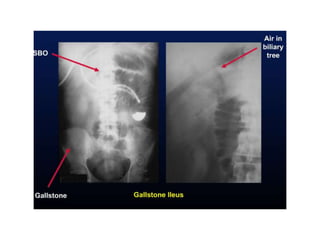

Gallstone ileus

• 2% of SBO

• Specific radiological signs in 40%

• High operative mortality

• Features

– Branching pattern of gas n biliary tree

– Gas in portal vein (peripheral)

– Obstructing gallstone in ileum

• Obscured by sacrum/overlying dilated gut

Biliary tree air Portal venous air

Gallstone ileus • 2%of SBO • Specific radiological signs in 40% • High operative mortality • Features – Branching pattern of gas n biliary tree – Gas in portal vein (peripheral) – Obstructing gallstone in ileum • Obscured by sacrum/overlying dilated gut

• 72.

Biliary tree airPortal venous air